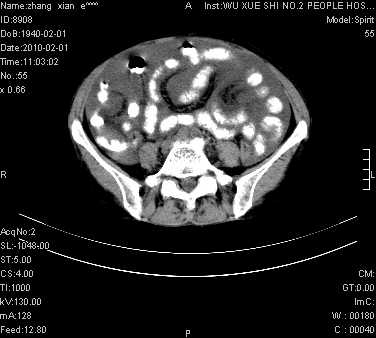

标题: CT24434:70岁 女 腹胀,腹水原因待查 [打印本页]

大量腹水,脾脏囊性占位,子宫颈占位,右侧腹股沟淋巴结肿大,建议+c,先查妇科。

腹盆腔大量积液,子宫增大,子宫颈增大外形不规则,内见低密度影,膀胱后壁显示不清,右腹股沟肿大淋巴结,脾脏囊性占位,子宫颈占位,子宫颈癌?建议增强。

考虑:1、腹膜转移,大量腹水;

2、脾占位性病变;

3、左侧卵巢占位性病变,建议增强进一步检查。